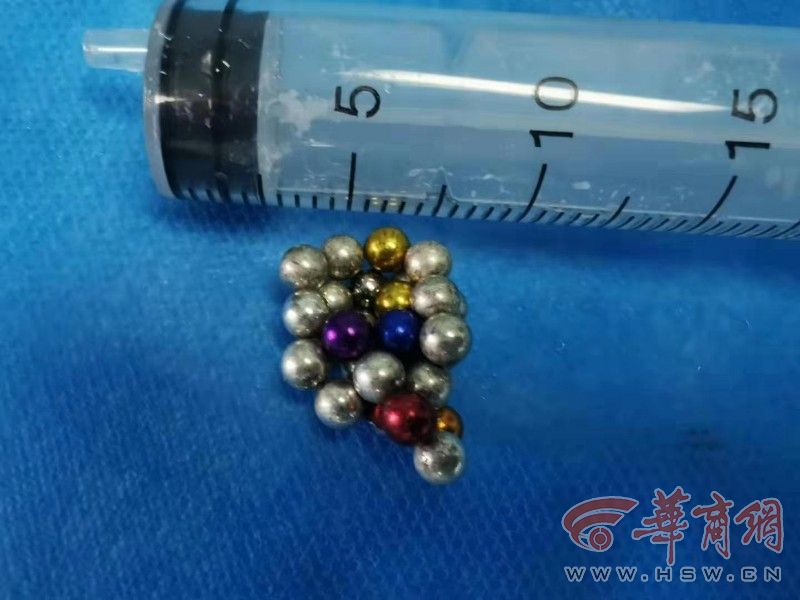

医生介绍说,这是巴克球,是一种圆形、光滑、具有磁性的金属球,直径在2毫米左右,很容易造成膀胱的穿孔、感染。

以往,这类异物要想取出来,需在患者肚皮上做开刀手术。但这样的创伤较大,患者很痛苦。这次,医生采取了经尿道微创手术,只用了十几分钟,便将进入男子体内、各种颜色的磁力球成功取出。数一数,居然有28颗。